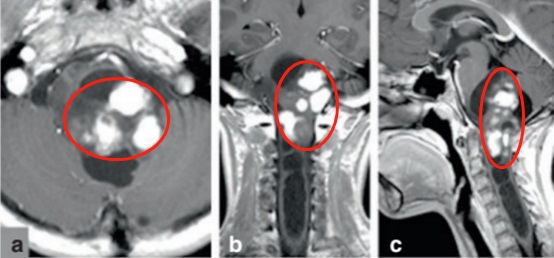

米亚在1岁半的时候就出现了轻微左侧偏瘫,她的父母觉察不对劲,果然去医院检查出了一个巨大的颅颈肿瘤。MRI上可以看出脑瘤起源于延髓后侧,由巨大的强化部分和邻近囊肿的非强化区组成。肿瘤已侵犯上段颈髓,达到 C3 水平,这导致占位性髓内空洞向下延伸至 T1 水平(图a、b、c)。